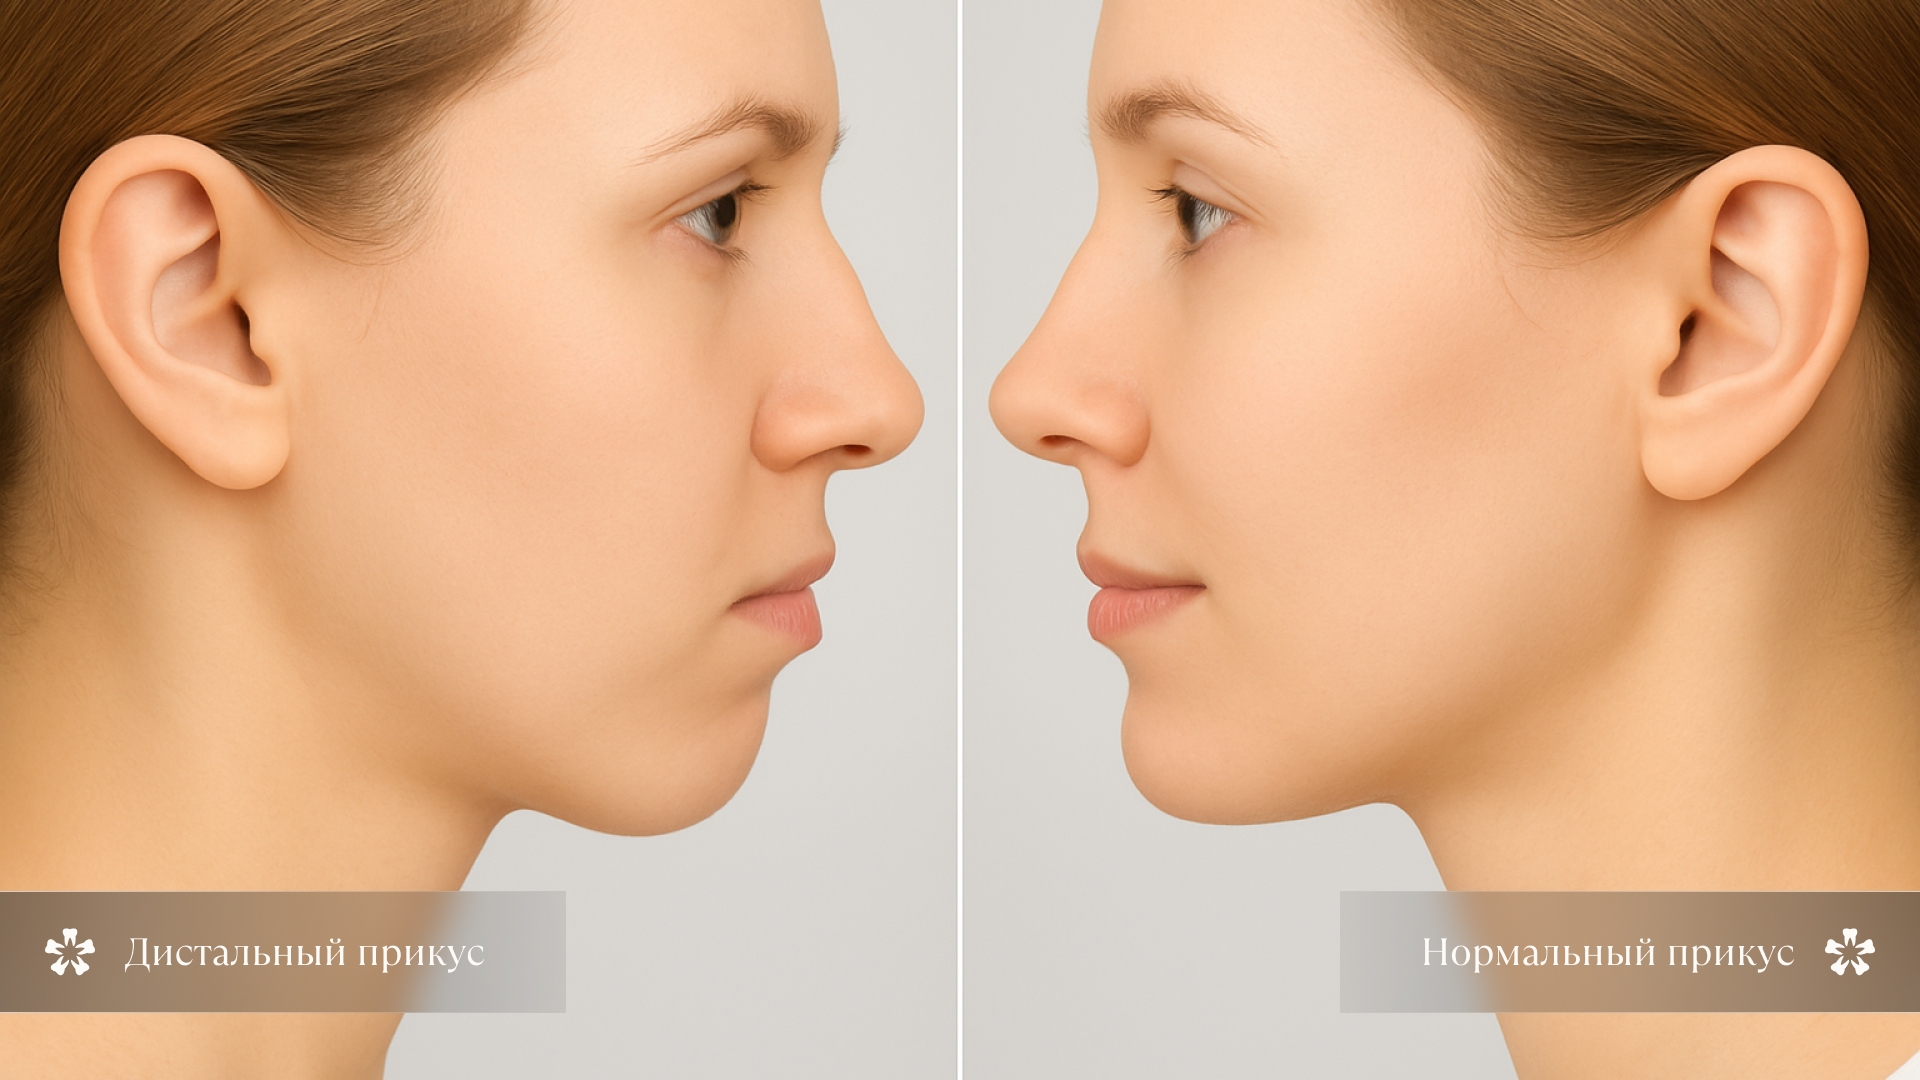

Дистальная окклюзия — это зубочелюстная аномалия, для которой характерно наличие диспропорции между положениями верхней и �нижней челюсти относительно друг друга. Чаще всего при этом выражено более переднее положение верхней челюсти относительно нижней.

1. Верхняя челюсть выступает вперед

За счет того, что скошен подбородок, меняются пропорции лица — профиль становится выпуклым, приобретает «птичий» вид.

2. Нижняя челюсть уходит назад

Нижняя челюсть у ребенка ушла назад. Возможно усиление складки над подбородком. Иногда бывает выражен «второй подбородок».